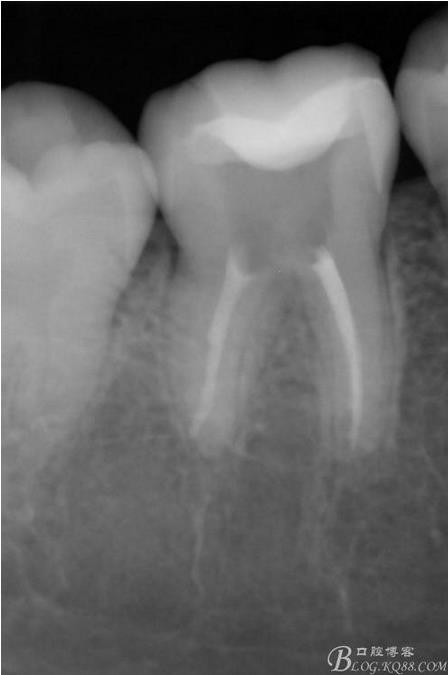

X線(xiàn):雙側(cè)下6 齲壞已接近髓腔

粘接后X線(xiàn)片